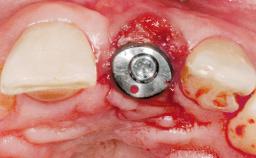

Immediate Flapless Placement of an Implant in a Maxillary Left Central Incisor Site

A 29-year-old female patient presented for treatment to replace the upper left central incisor tooth with an implant- supported restoration. The tooth had been intermittently symptomatic for the previous 12 months. The tooth had originally suffered trauma about 15 years previously. Several endodontic treatments had been performed, including an apicectomy procedure to retain the tooth. The patient was healthy and a non-smoker. She had reasonable expectations in regard to esthetic outcomes and the risk of marginal tissue recession following treatment. At medium smile, the gingival margins of the upper teeth were visible, with a display of 3 to 4 mm of the gingival margins. Gingival recession of tooth 21 and a discrepancy in the gingival levels between teeth 11 and 21 was observable during normal speech and smile.

Placement Protocol Immediate implant placement

Tooth Site Maxillary incisor or canine

Socket Morphology Single-root socket

Socket Integrity Damage to one or more bone walls

Bone Volume Damage to one or more socket walls